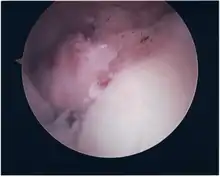

Surgical treatment of SLAP tears has become more common in recent years. The success rate for repairing isolated SLAP tears is reported between 74-94%.[7] While surgery can be performed as a traditional open procedure, an arthroscopic technique[8] is currently favored being less intrusive with low chance of iatrogenic infection.[9]

Procedure

Following inspection and determination of the extent of injury, the basic labrum repair is as follows.

- The glenoid and labrum are roughened to increase contact surface area and promote re-growth.

- Locations for the bone anchors are selected based on number and severity of tear. A severe tear involving both SLAP and Bankart lesions may require seven anchors. Simple tears may only require one.

- The glenoid is drilled for the anchor implantation.

- Anchors are inserted in the glenoid.

- The suture component of the implant is tied through the labrum and knotted such that the labrum is in tight contact with the glenoid surface.